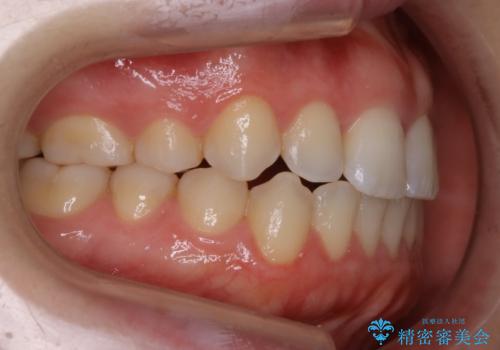

【非抜歯】上下の前歯が噛み合わないオープンバイトの治療

- 噛み合わせの不調を主訴にご来院されました。

骨格的な問題もあり、噛んだ時に奥歯しか当たらず前歯の被蓋があまりない状態でした。

臼歯の位置が高く噛んだ時に奥歯しか当たらなかったり、舌癖などが原因で前歯が前に倒れてしまうことで上下の前歯の被蓋がなくなってしまっている状態をオープンバイトといいます。

前者の場合は臼歯を圧下し沈めてあげることで改善させます。後者の場合は前方に傾斜している歯を元の角度に戻してあげることで改善しますが、舌癖がある場合はその癖自体を無くす治療をしない限りまた同じ状態へと後戻りしてしまいます。